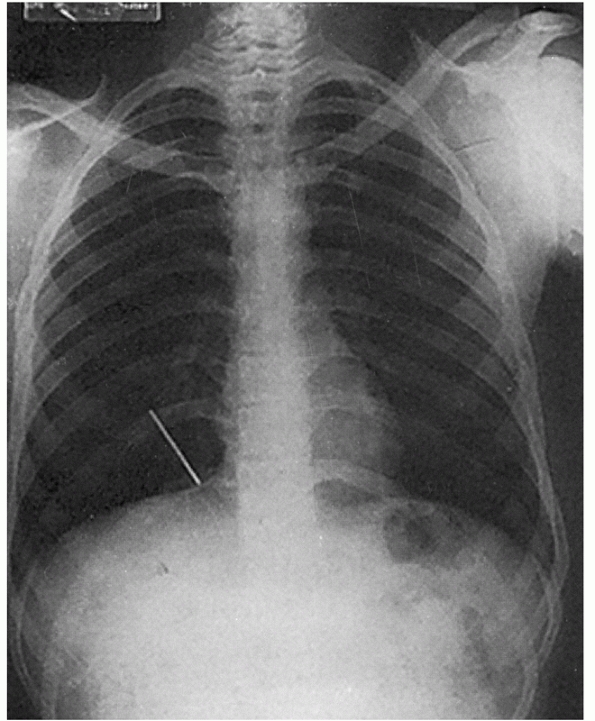

of type V injuries is a marked increase (100% to 300%) in the

coracoclavicular interspace. The clavicle appears to be grossly

displaced superiorly away from the acromion (Fig. 39-14).

However, radiographs reveal that the clavicle on the injured side is

actually at approximately the same level as the clavicle on the normal

side, and the scapula is displaced inferiorly.